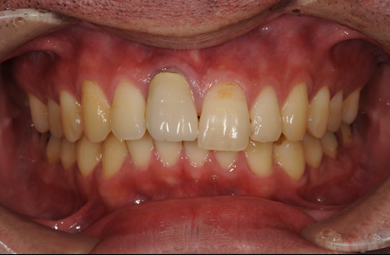

インプラントの症例写真 IMPLANT

| 治療内容 | インプラント1本(抜歯即日スピードインプラント)、メタルボンドセラミック1本 | ||||||||||||||||||||||||||||||||

| 治療期間 | 5ヶ月 |